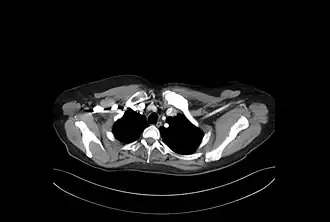

- et de manifestations ostéo-articulaires, atteignant essentiellement la paroi thoracique antérieure et l'ensemble sterno-claviculaire :